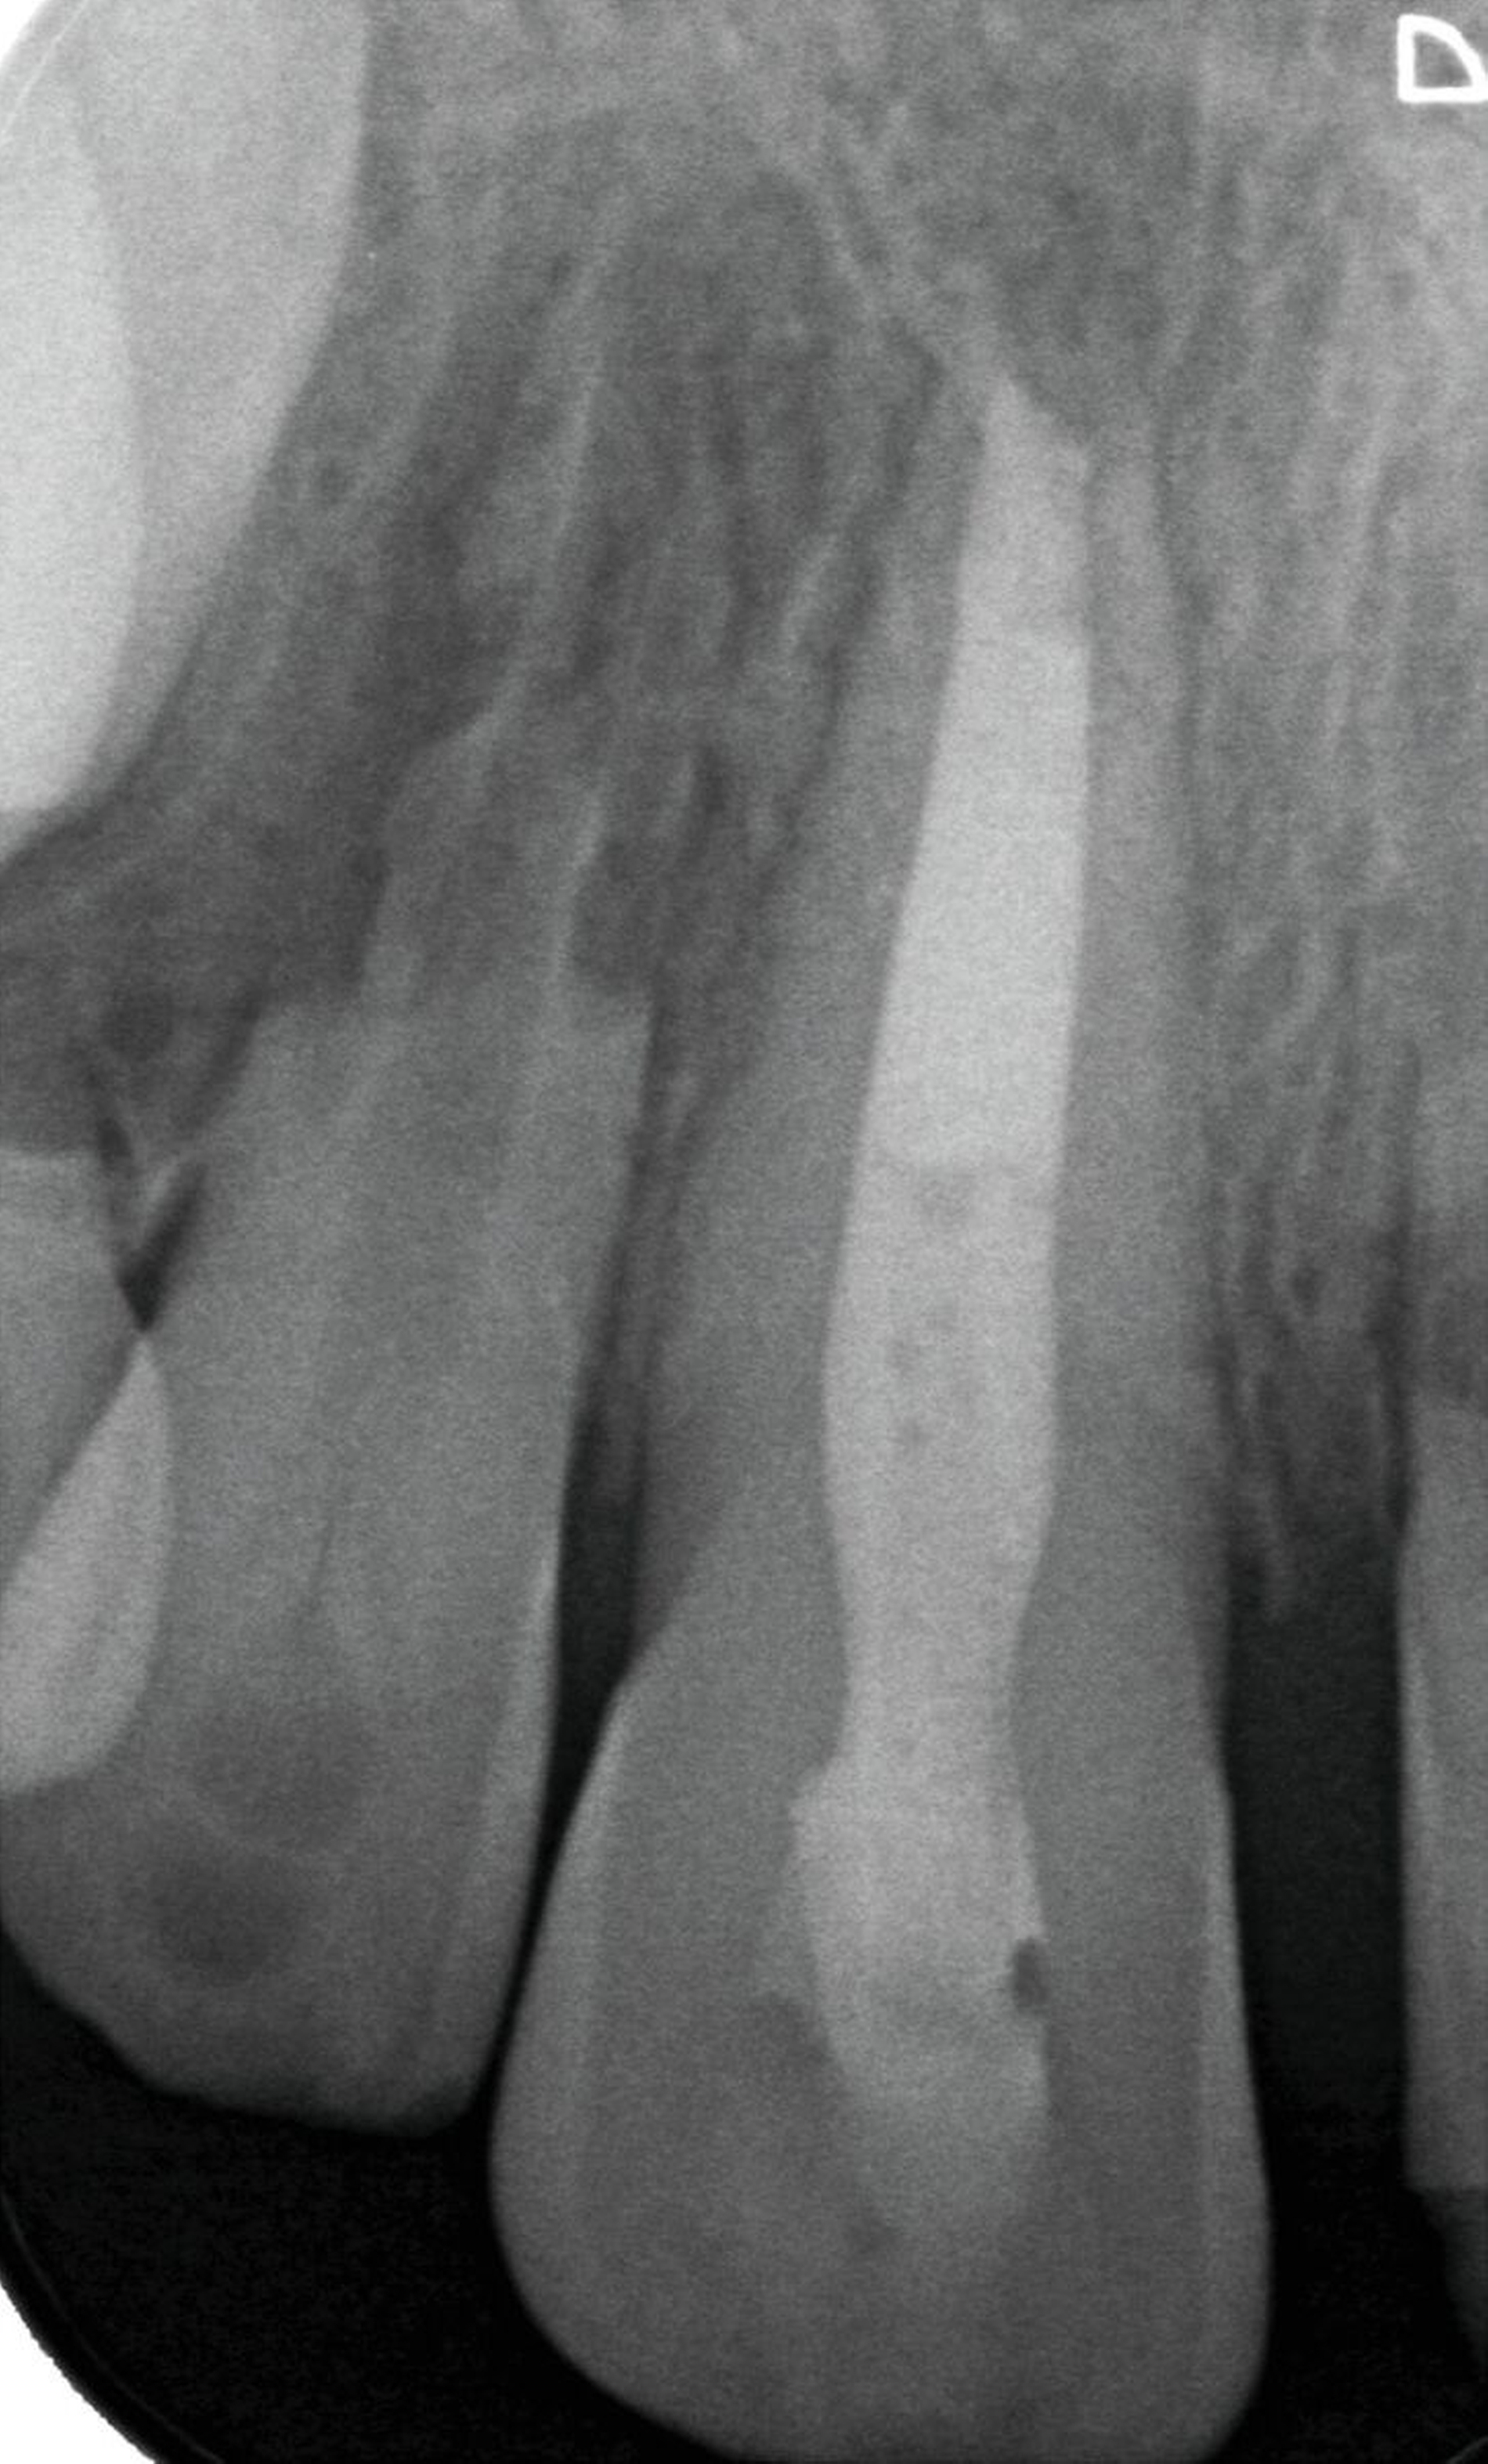

Bei allen Varianten der progressiven internen Resorption ist grundsätzlich eine endodontische Intervention erforderlich. Nach Entfernung des resorbierenden Gewebes aus dem Wurzelkanal kann dieses sorgfältig desinfiziert und gefüllt werden (Abbildung 9). Wenn der Resorptionsdefekt die Wurzelkanalwand durchbrochen hat, sollten bioaktive hydraulische Kalziumsilikatzemente wie Mineral Trioxide Aggregate (MTA) zur Reparatur verwendet werden. Im Fall einer Perforation kann auch eine chirurgische Behandlung von außen erforderlich sein. Die Prognose für den betroffenen Zahn hängt von der Position, der Größe und dem Infektionsgrad des Defekts ab. Ist die Zahnerhaltung aufgrund eines erheblichen Substanz- und Stabilitätsverlusts nicht mehr möglich, ist eine Extraktion unumgänglich [Nilsson et al., 2013].

Die erfolgreiche Therapie invasiver zervikaler Resorptionen umfasst grundsätzlich die vollständige Entfernung des Granulationsgewebes. Zu den Behandlungsoptionen gehören die externe Reparatur ohne Wurzelkanalbehandlung, die interne Reparatur mit Wurzelkanalbehandlung, die intentionelle Replantation oder die regelmäßige Kontrolle mit Sensibilitätstests bei asymptomatischen, nicht restaurierbaren Fällen (Abbildungen 10 und 11). Die Extraktion stellt die einzige Behandlungsoption für nicht restaurierbare, symptomatische Läsionen dar [Patel et al., 2018].